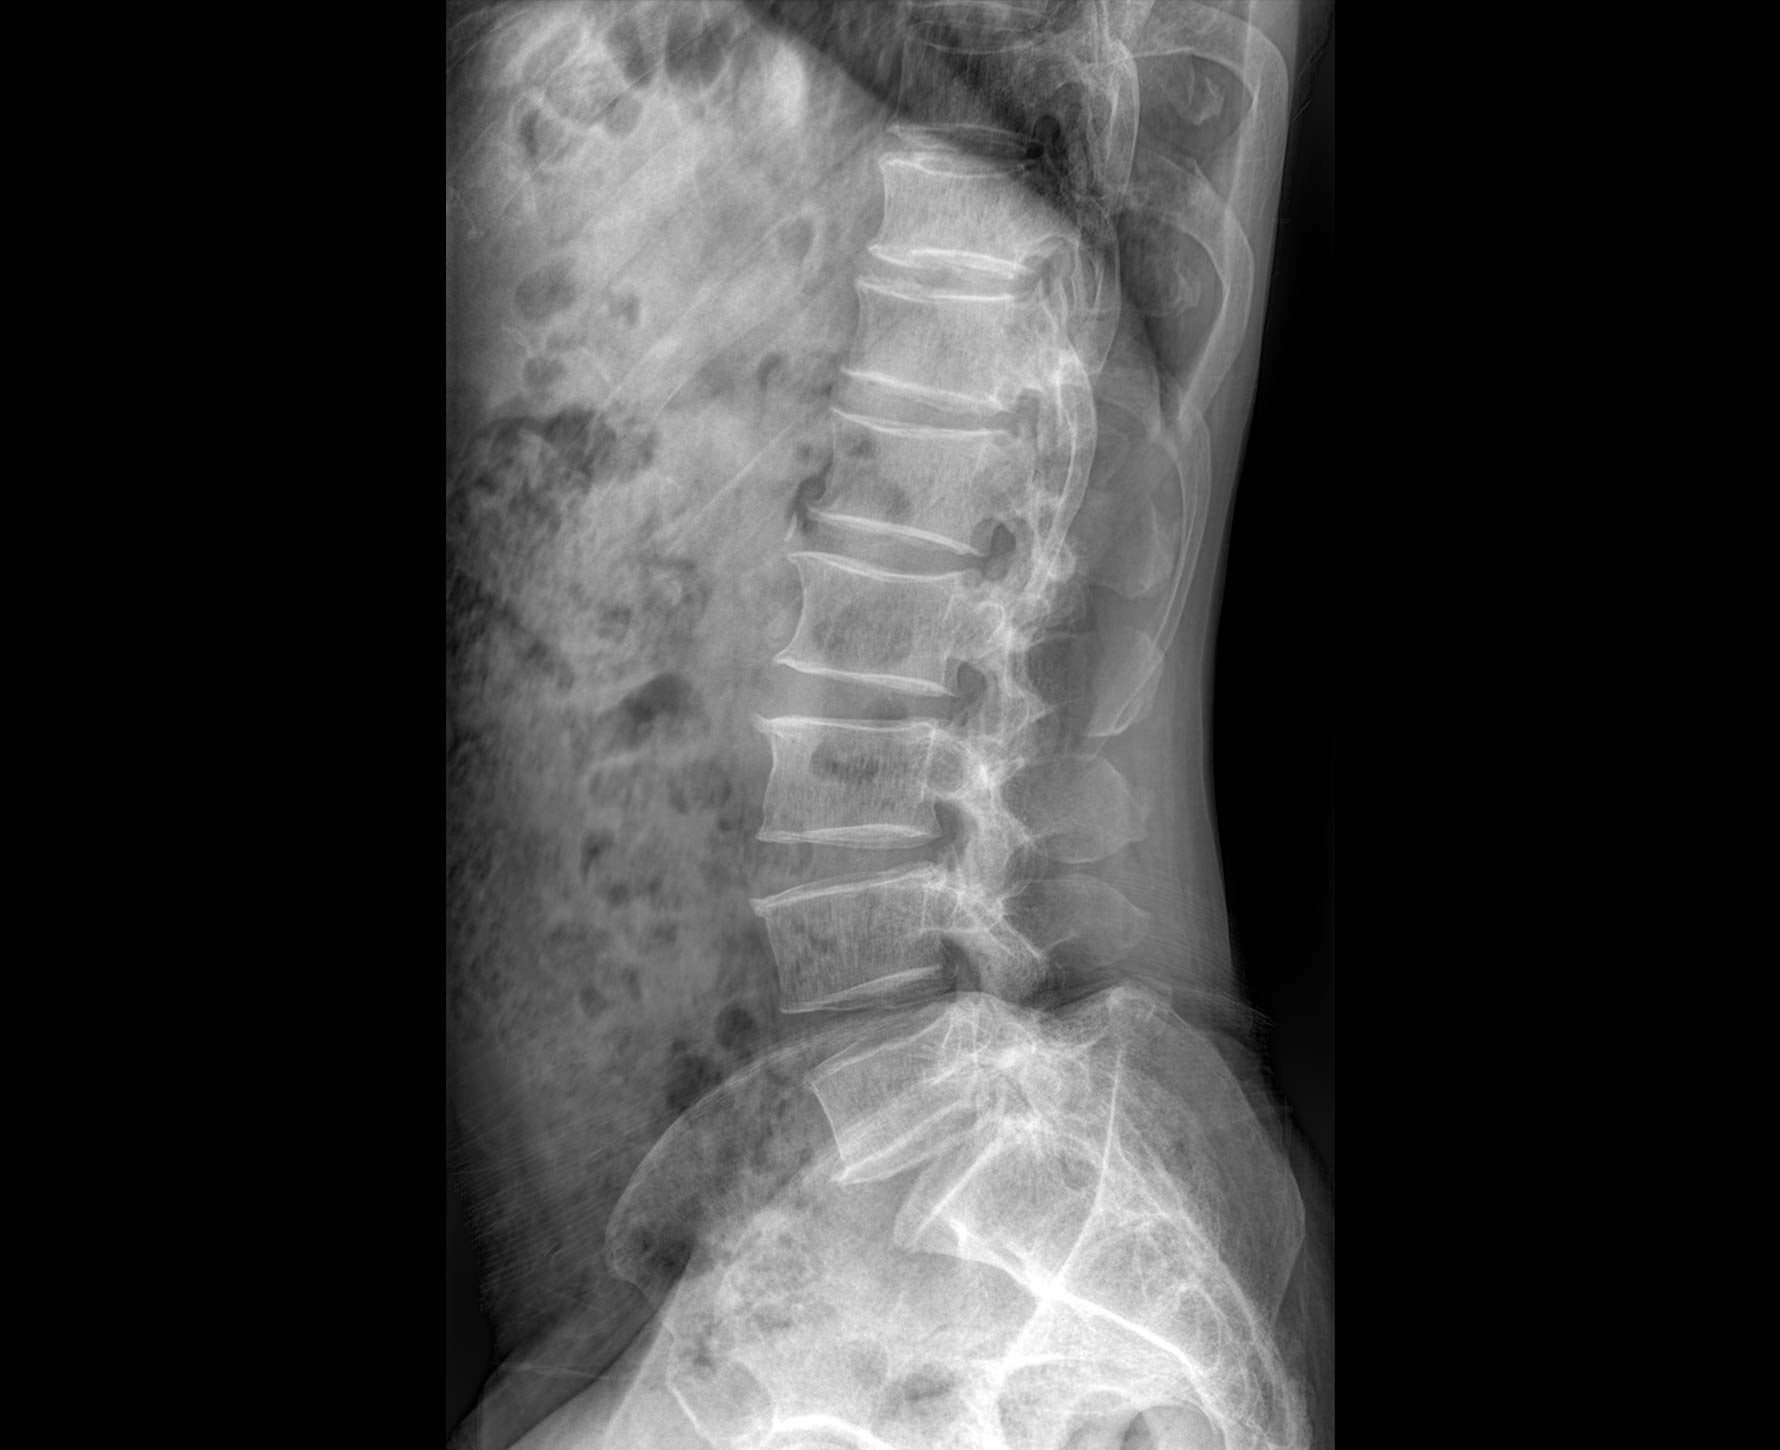

临床图像